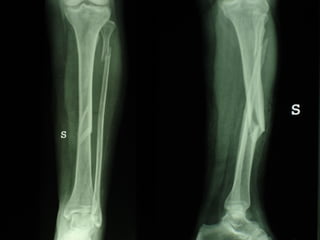

Dal Gennaio 2000 al Febbraio 2006 abbiamo trattato 167 fratture chiuse  con placca percutanea  in 164 pazienti :  27 lesioni diafisarie di gamba, 12 piloni tibiali ,  11 fratture prossimali di tibia, 36 fratture sovracondiloidee di femore, 17 fratture diafisarie di femore, 43 fratture metaepifisarie prossimali di omero, 21 diafisarie d’omero.  156 guarigioni 8 fallimenti

I buoni risultati ottenuti dipendono da 5 punti fondamentali:   una accurata riduzione percutanea della frattura  precise vie di accesso  l’utilizzo della placca che consenta il più lungo braccio di leva possibile il pretensionamento della placca  una sintesi con un ridotto numero di viti

Placche lunghe e pretensionate

Placche lunghe e pretensionate Sintesi con un ridotto numero di viti